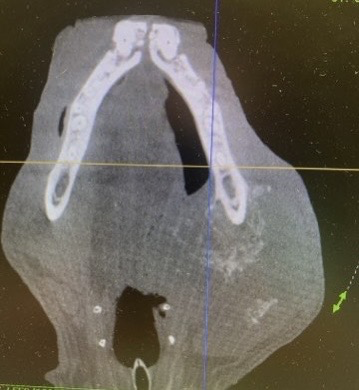

While dental radiographs are important, we are pleased to announce that we will be offering Cone Beam Computed Tomography (CBCT). Our state-of-the-art Germantown clinic has the capability to take three-dimensional images of your pet’s mouth and teeth. This will allow even more accurate diagnosis and improve patient treatment planning.